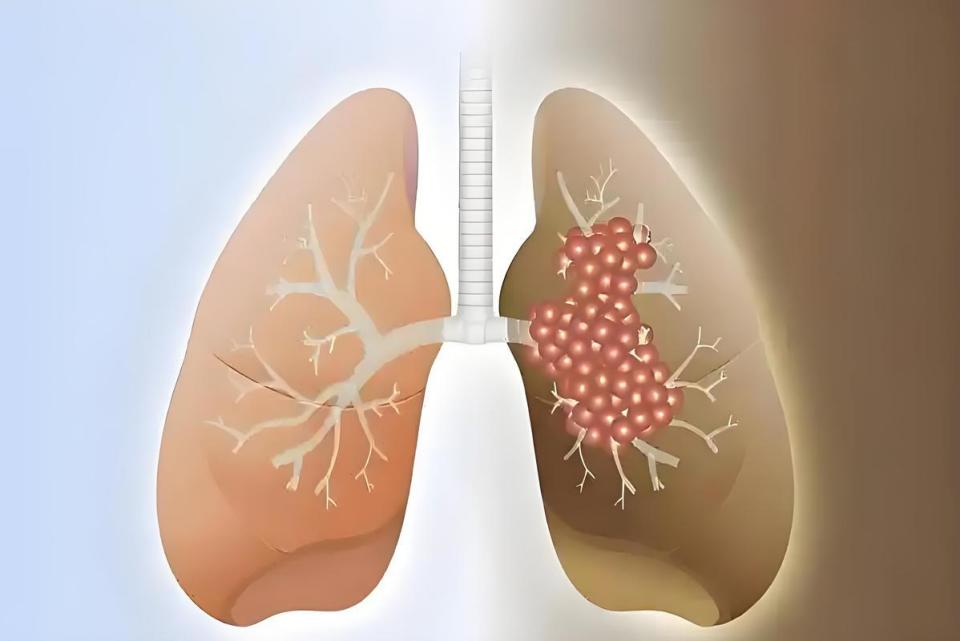

特别提醒:这些“肺结节”可能是定时炸弹

并非所有肺结节都会癌变,但出现以下特征需警惕:

· 大小:直径>8mm的实性结节

· 形态:边缘毛刺、分叶、空泡征

· 生长速度:3个月内体积增大25%

· 密度:混合磨玻璃结节癌变率达63%